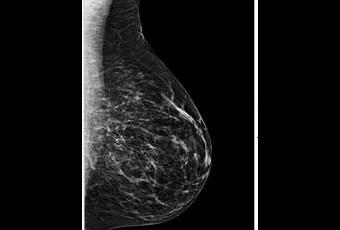

La participation de la population féminine cible du dépistage généralisé du cancer du sein, par mammographie, est restée stable en 2011, déplore quelque peu l'Institut de veille sanitaire qui rappelle que le plan cancer 2009-2013 avait fait de l'augmentation de 15% de la participation au dépistage , une de ses ambitions phares. Dans le cadre de cette stabilité nationale, avec une participation moyenne de 52,7%, de fortes disparités régionales transparaissent dont un taux à Paris qui peine à atteindre les 28%. Ces résultats, insuffisants, dans le cadre de la stratégie française actuelle de dépistage, sont publiés alors que dans d'autres pays, le principe même du dépistage organisé du cancer du sein est de plus en plus controversé.

Un taux de participation insuffisant, selon l'InVS : Généralisé à l'ensemble du territoire en 2004, ce dépistage concerne de plus en plus de femmes mais son taux de participation en augmentation jusqu'en 2008 a atteint depuis un palier ne parvenant pas à excéder les 53%, bien en deçà de l'objectif européen de 70%. De plus la participation au dépistage organisé reste inégale selon les régions allant de taux à 60% (Pays-de-la-Loire, Limousin, Bretagne, Centre) à 27,4% à Paris, où la participation au dépistage reste la plus faible. Alors que 10% de la population cible effectue un dépistage individuel « de son côté », l'InVS conclut donc à un taux global de 65% toujours inférieur à l'objectif européen.

La France reste très favorable à ce programme de dépistage généralisé et gratuit, bénéficiant d'une double lecture des mammographies. Mais, ces dernières années, tant aux Etats-Unis qu'au Royaume-Uni, ce dépistage systématique du cancer du sein est remis en cause en raison de son risque de sur-diagnostic et de sur-traitement et du peu d'impact du dépistage en termes de mortalité. La dernière étude en date, publiée il y a quelques jours dans les Annals of Internal Medicine indique que dépister par mammographie 2.500 femmes permettrait d'éviter un décès par cancer du sein.